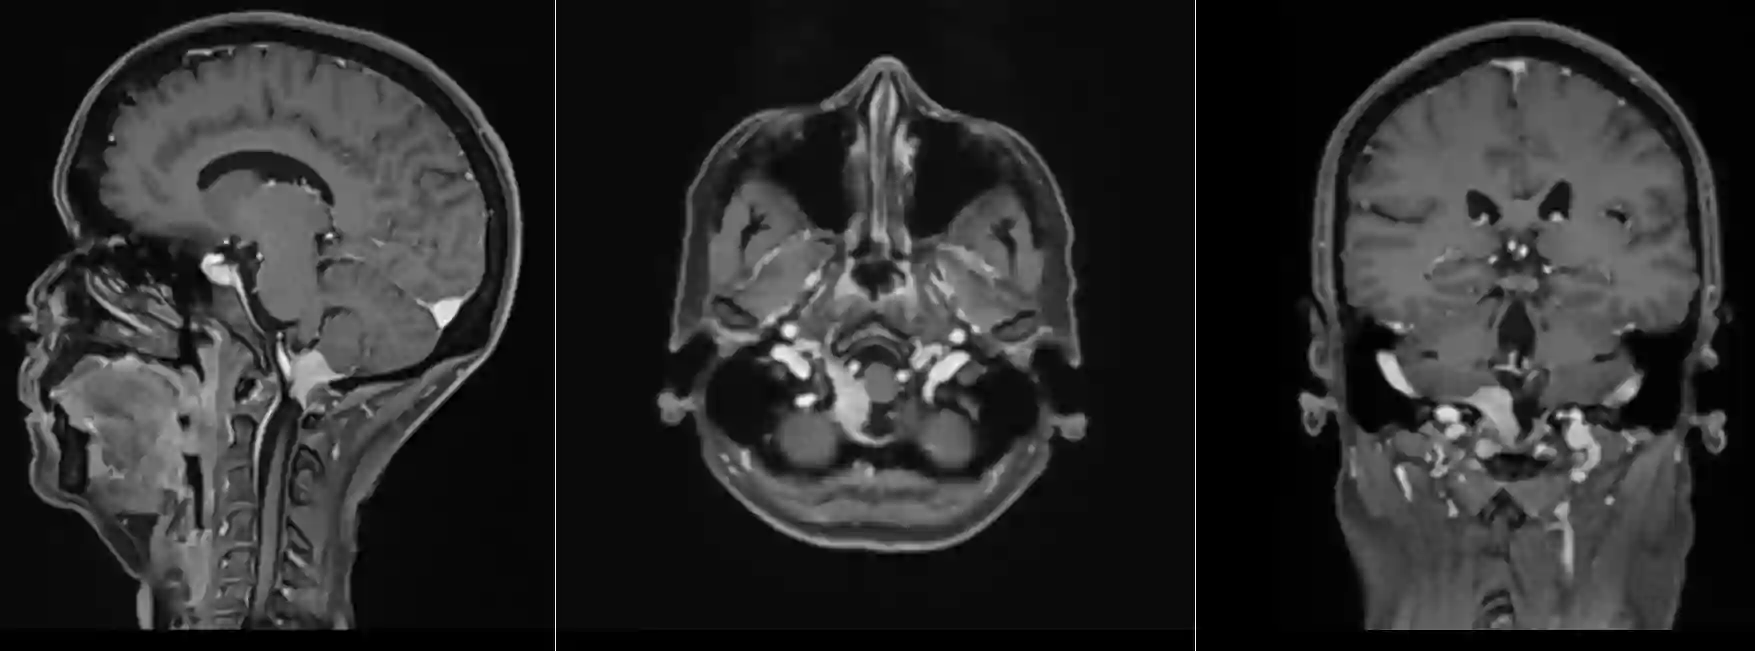

Foramen magnum Meningeom im MRI

T1 Sequenz mit Kontrastmittel eines Foramen magnum Meningeoms in drei verschiedenen Ebenen.